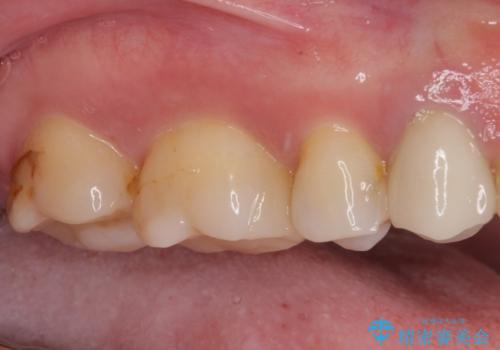

- 奥歯の詰め物や周辺の歯が欠けてしまったとのことで来院された患者様です。

上顎は、元々の詰め物が小さく、欠けた範囲も大きくなかったため、セラミックインレーにて修復治療を行うこととしました。

一方下顎は、元々のむし歯の範囲が広かったため、長期的な予後を踏まえ、セラミッククラウンにて補綴治療を行うこととしました。

特に痛みはありませんでしたが、未然にしっかりとした処置を行うことで、今後むし歯の進行により神経組織が壊死するリスクを低減することが可能となります。